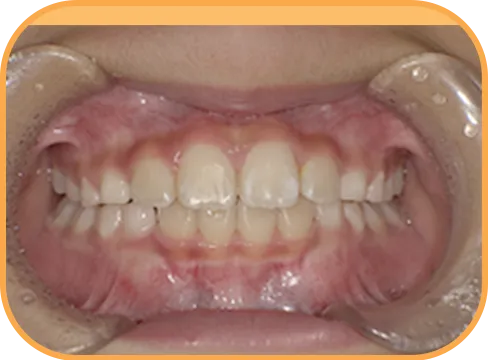

• 正 面

治療後正面からの歯の様子

主 訴

上の前歯がねじれている、ガタガタ

治療内容

インビザライン・ファースト

治療期間

8か月

治療費(税別)

450,000円+診断料50,000円

リスク・副作用

• 親知らずの影響や加齢などによって、凸凹が生じる可能性があります。

• 治療の初期段階では痛みや不快感が生じやすくなりますが、1週間前後で慣れます。

• 顎の成長発育によって、噛み合わせや歯並びが変化する可能性があります。

• 状況により当初予定した治療計画を変更する可能性があります。